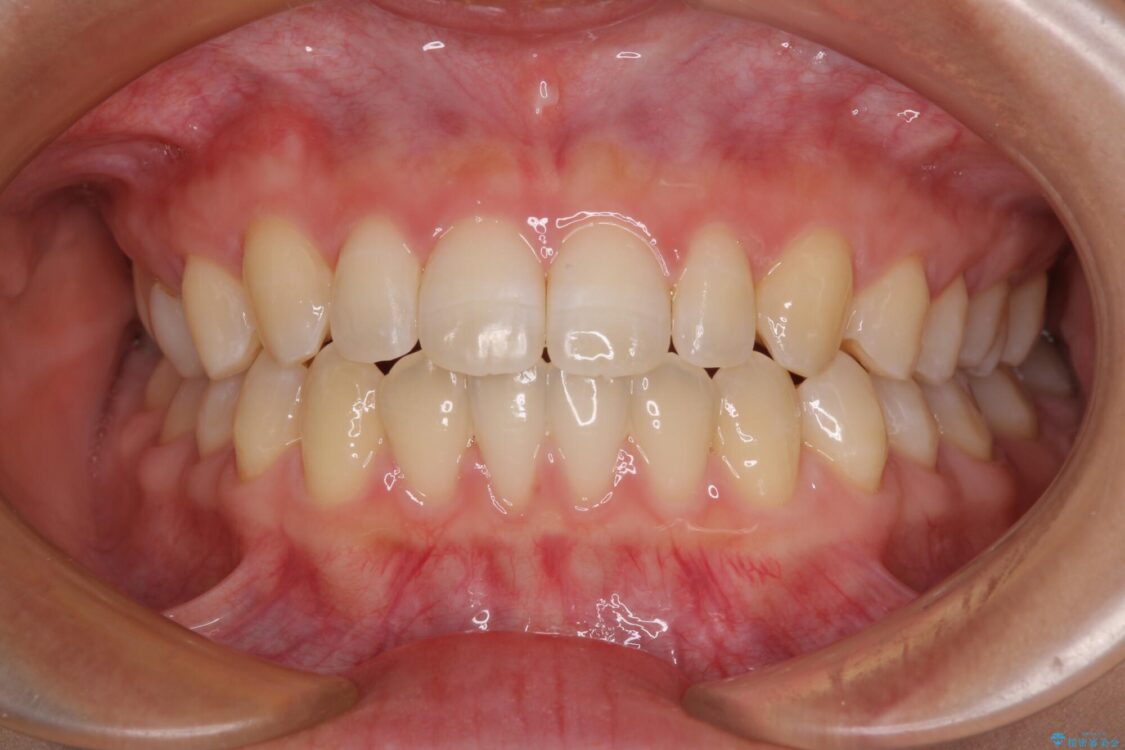

治療後

• 隙間だらけの歯列 インビザラインで改善 治療後画像